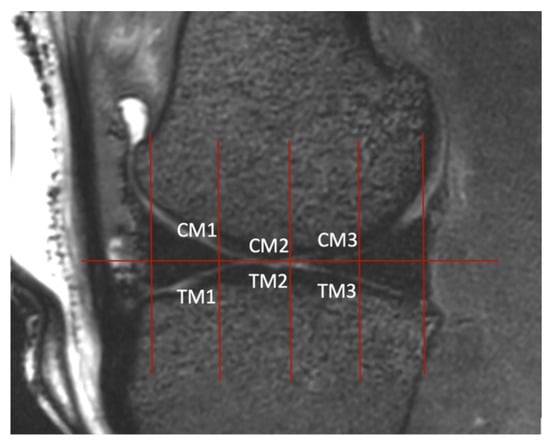

Figure 6. Sagittal view of the medial femorotibial joint in a 3D T2-weighted VIEW image where the regions of interest (ROIs) were determined. The sagittal plane was set as described in Figure 5. In this view, two lines were drawn. The first one passed vertically through the largest extent of the cranial aspect of the meniscus and the second passed through the caudal aspect. The distance between these two lines was quartered by drawing three lines that were parallel to the first two. Where these lines intercepted the cartilage, the thickness was measured (ROIs CM1, CM2, CM3, TM1, TM2, TM3). This was carried out for the lateral femorotibial joint as well.